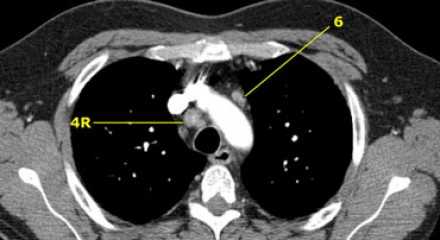

На изображении слева мы видим 4R паратрахеальные узлы. Кроме того здесь представлен узел кнаружи от дуги аорты, то есть 6 группы.

4L. Левые нижние паратрахеальные лимфатические узлы

4L узлы расположенные слева от левой стенки трахеи, между горизонтальными линиями проведенными касательно верхней стенке дуги аорты и линией проходящей через левый главный бронх на уровне верхнего края верхнедолевого бронха. Они включают паратрахеальные узлы расположенные кнутри от артериальной связки.

Узлы 5 группы (аортопульмонального окна) расположены кнаружи от артериальной связки.